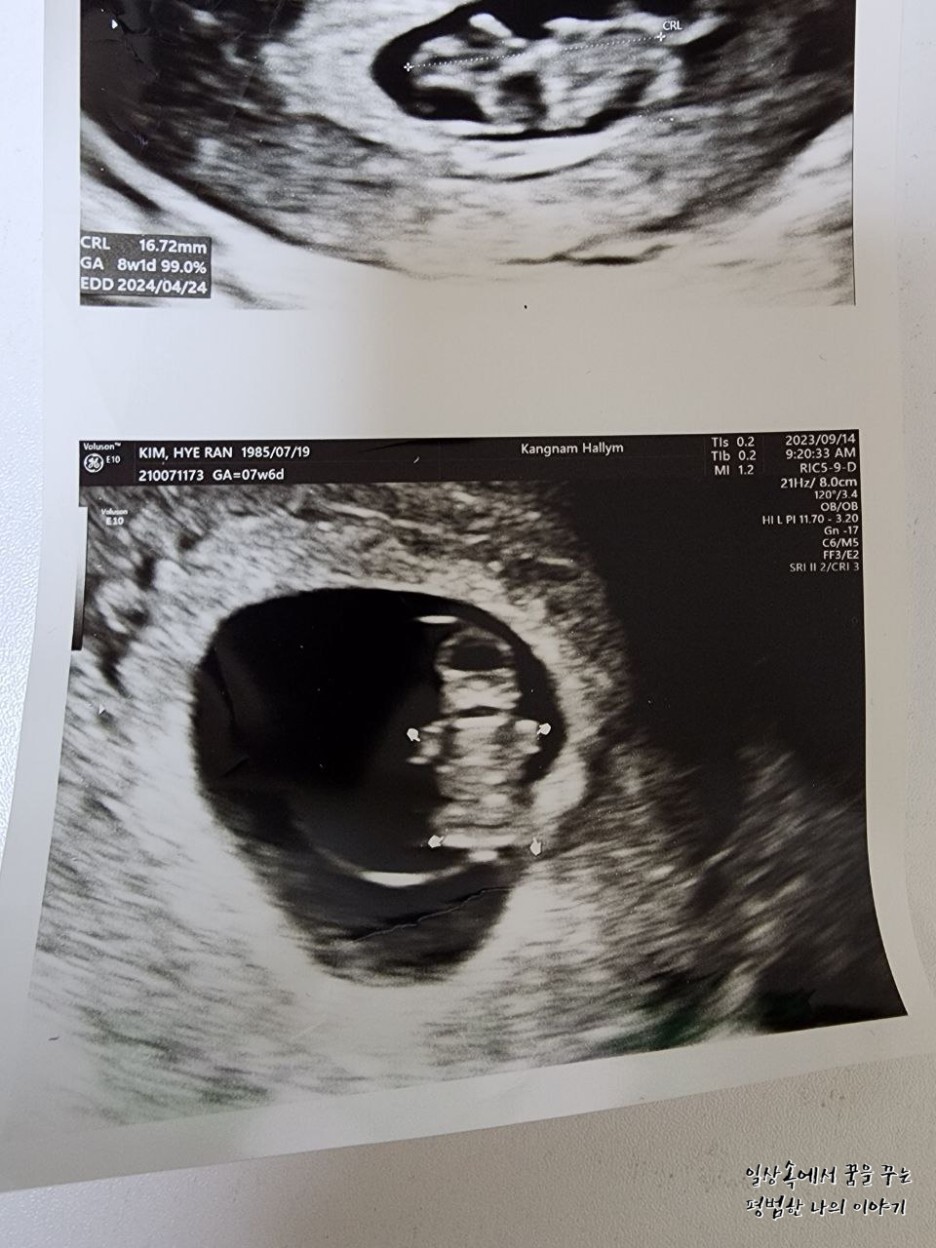

레오나의 CRL(=Crown-Rump Length, 태아의 머리부터 엉덩이까지의 길이)은 16.72mm로 평균보다 살짝 컸지만 원래 낳기 전까지 크기는 계속 변하기 때문에 크게 의미를 두지 않아도 될 것 같다.

EDD(Expected Date of Delivery, 출산 예정일)는 보통 12주 전후에 결정되는 날짜가 의미를 가진다. 물론 출산 예정일에 출산을 하는 경우는 드물지만 보통 그 날짜를 바탕으로 출산 계획을 짜면 되더라. 나는 첫째를 40주 차에 유도 분만으로 낳았기 때문에 이번에도 왠지 그럴 것 같은 기분이...